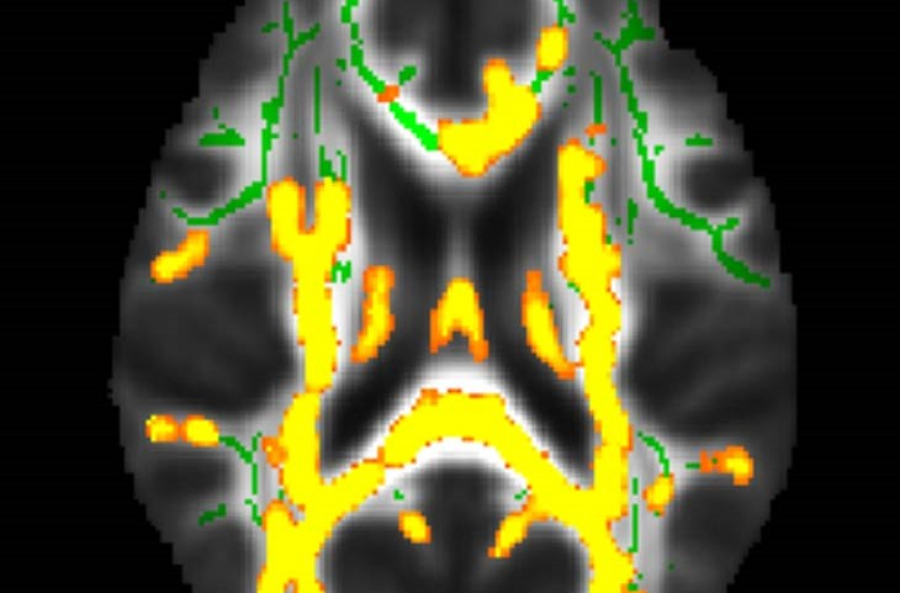

Οι μεγαλύτερες ποσότητες σπλαχνικού λίπους στη μέση ηλικία συνδέονται με την ανάπτυξη της νόσου Αλτσχάιμερ, σύμφωνα με έρευνα που θα παρουσιαστεί στο ετήσιο συνέδριο της Ακτινολογικής Εταιρείας της Βόρειας Αμερικής.